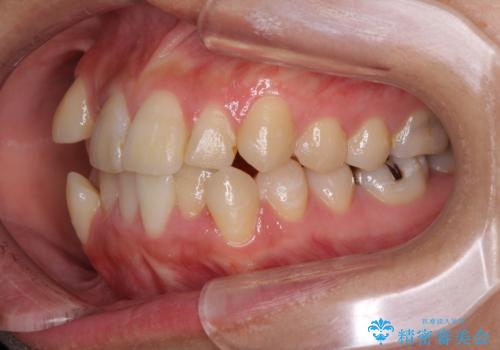

右側のみ上下小臼歯を抜歯したため、上下の正中が右にずれてしまう可能性があります。

また、元々右側は上下が咬み合っていないため、矯正をしても咬み合わないことも考えられました。

治療期間はかかりましたが、正中も合い、綺麗な仕上がりとなりました。